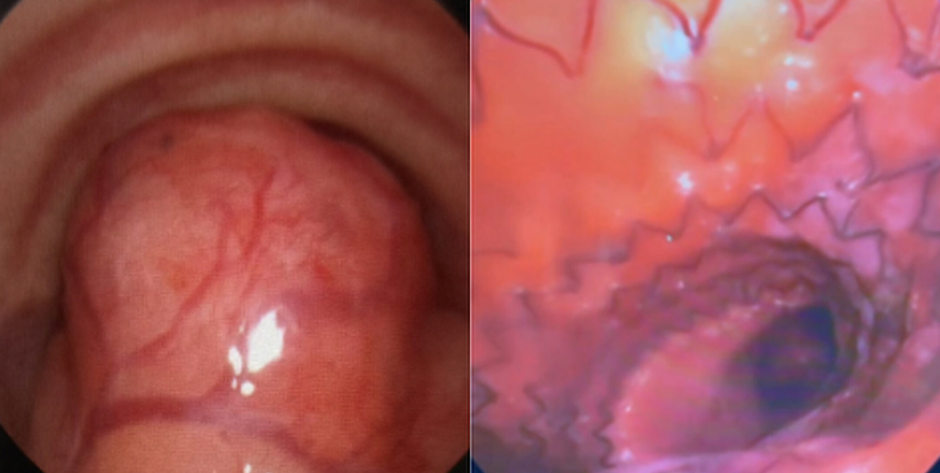

Пациент 33 лет с позиционной одышкой, с трудом говорит длинными фразами. Жалобы на усугубляющиеся на протяжении последнего года одышку и нарушения сна. При осмотре выявлен двухфазный стридор в покое, но SpO2 составила 97%.

При трансназальной трахеоскопии обнаружили рыхлое новообразование в задне-среднедистальном отделе трахеи, практически полностью перекрывавшее просвет. Для подтверждения находки выполнили бронхоскопию и КТ.